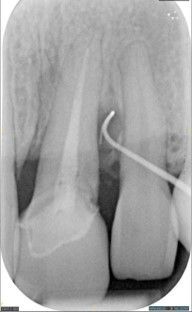

Case 1 - Upper incisor and bone loss due to root fracture after trauma to the tooth. Replaced with dental implant and simultaneous bone grafting